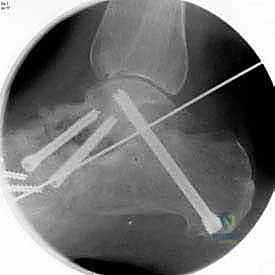

5. التثبيت الداخلي (Internal Fixation)

بعد التأكد من الوضعية المثالية للعظام، يتم تثبيتها بقوة باستخدام مسامير معدنية مجوفة من التيتانيوم (Cannulated Screws) أو شرائح معدنية خاصة. يتم إدخال المسامير تحت توجيه الأشعة السينية المباشرة (Fluoroscopy) داخل غرفة العمليات لضمان الدقة المتناهية. هذه المسامير تضغط العظام معاً وتمنع أي حركة حتى يحدث الالتئام التام.